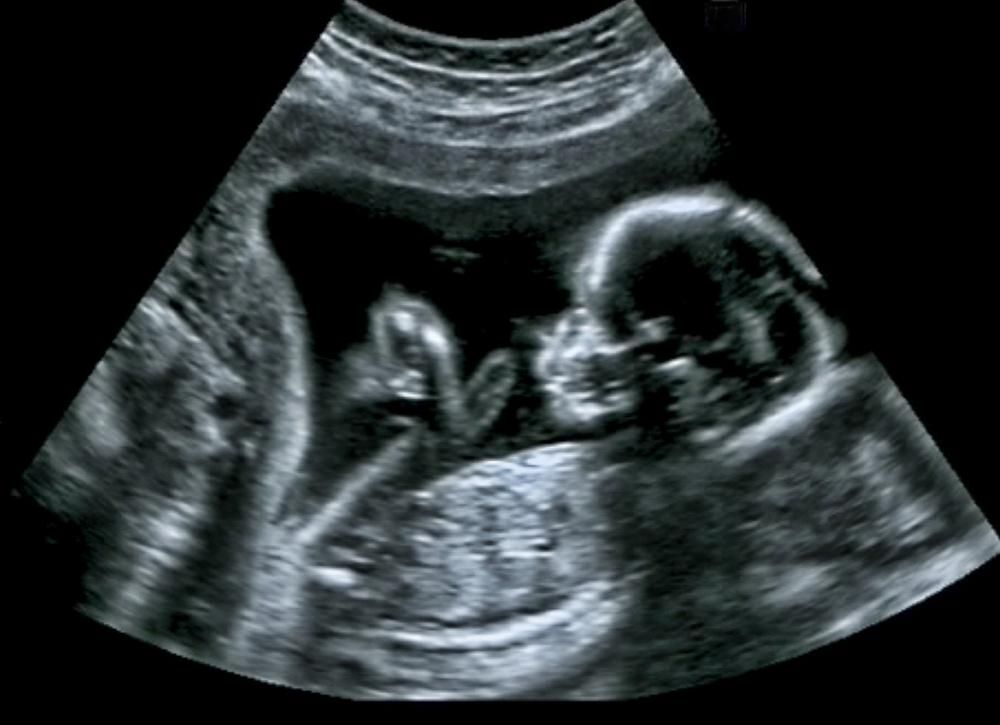

A kutatók azt vizsgálták, hogyan reagáltak a magzatok a sárgarépa vagy a kelkáposzta ízére, röviddel azután, hogy azokat az anyák elfogyasztották. A sárgarépa ízének kitett magzatok több „nevetős-arc”, míg a kelkáposzta ízének kitett magzatok több „sírós-arc” reakciót mutattak.

A kutatócsoport, amelyben a birminghami Aston Egyetem (Egyesült Királyság) és a franciaországi Burgundiai Nemzeti Tudományos Kutatóközpont - Burgundiai Egyetem tudósai is részt vettek, a 18 és 40 év közötti anyákat a terhesség 32. és 36. hetében is szkennelte, hogy lássák a magzatok arcának reakcióit a kelkáposzta- és sárgarépa ízekre.

A mindkét ízesített csoportban megfigyelt arcreakciók, összehasonlítva a magzatokkal egy kontrollcsoportban, akik nem voltak kitéve egyik íznek sem, azt mutatták, hogy már kis mennyiségű sárgarépa- vagy kelkáposztaíznek való kitettség is elég volt ahhoz, hogy reakciót váltson ki.